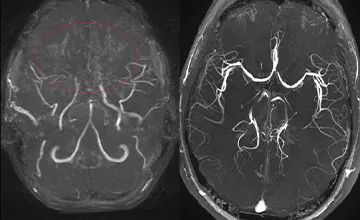

- Maladie et Syndromes de Moya-Moya